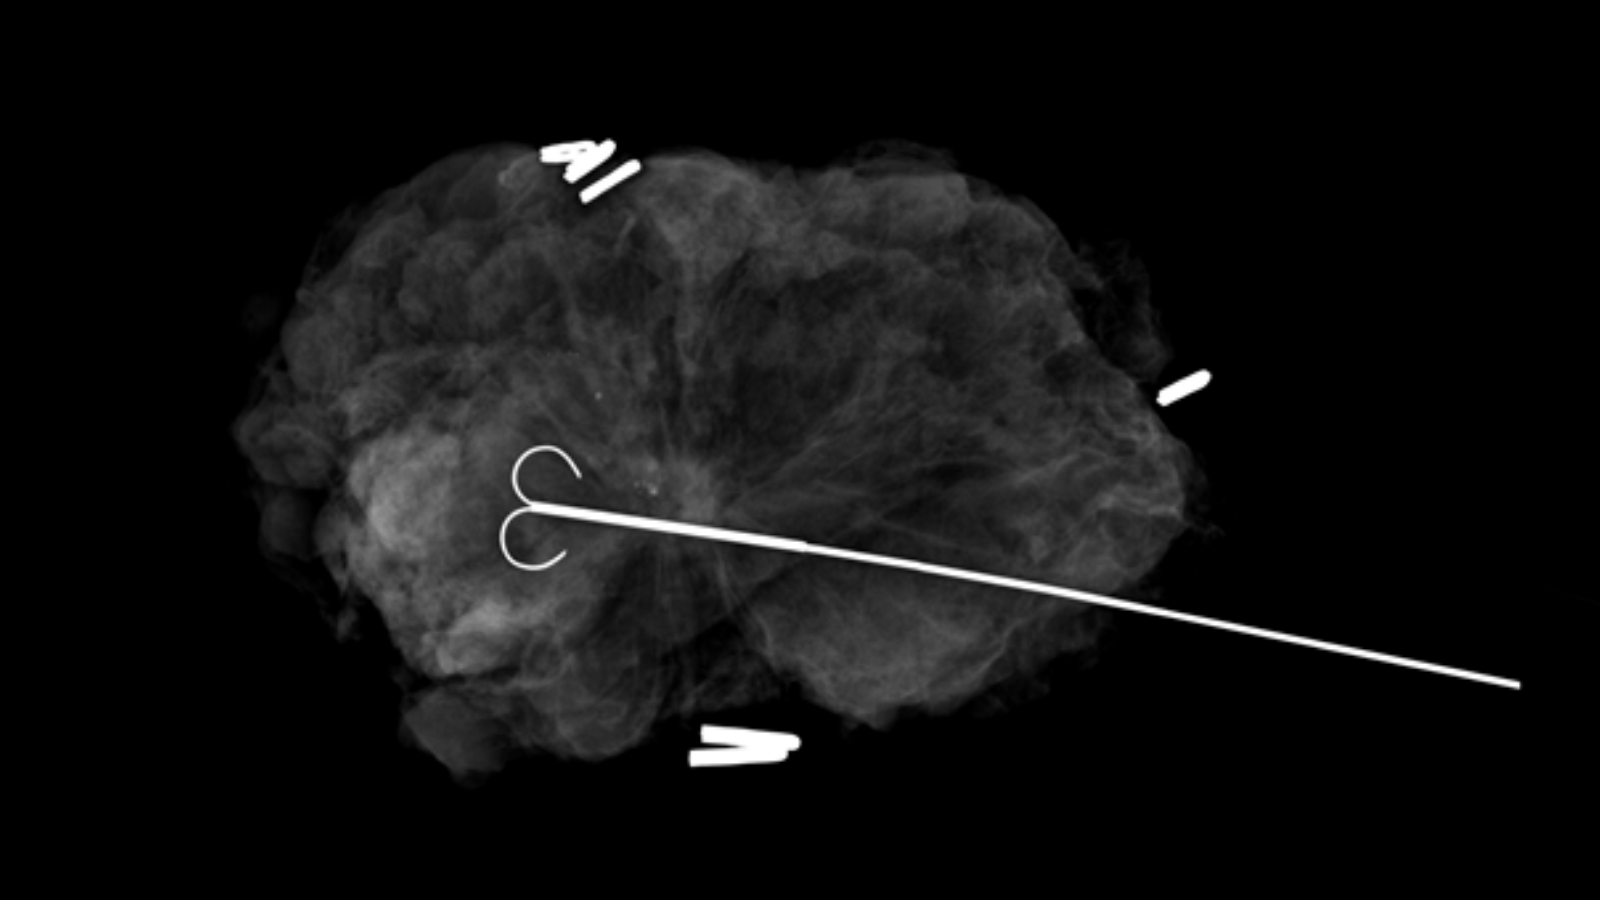

Specimen radiography showing a lumpectomy with a radioactive seed... Download Scientific Diagram

Specimen radiography showing a lumpectomy with a radioactive seed... Download Scientific Diagram Specimen Radiograph Definition Localisation of the malignant lesions was. Detects bone fractures, certain tumors and other abnormal masses, pneumonia, some types of injuries, calcifications, foreign objects, or dental problems. Two women underwent stereotactic sampling of mammographically detected lesions with insertion of breast biopsy markers. Other techniques that may occasionally aid the surgical pathologist in tumor diagnosis. Review of specimen radiographs is one of. Specimen Radiograph Definition.